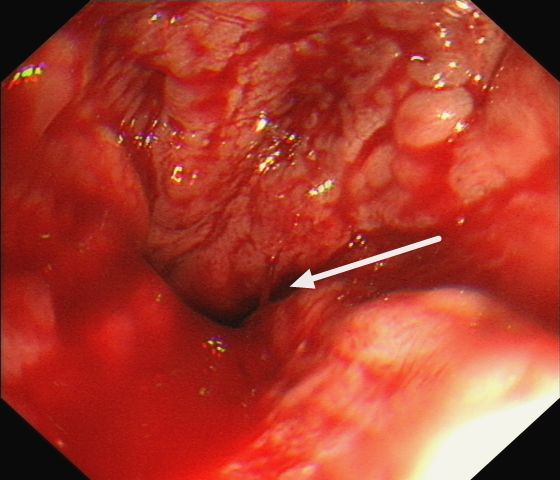

胃镜下可见明显“血柱”

医生立即决定完善急诊胃镜检查,患者内镜下食管静脉曲张如藤蔓一般盘根错节,可见一处“血柱”像喷泉一样源源不断涌出,此时内科药物治疗已难以达到止血目的。

术后胃镜图片